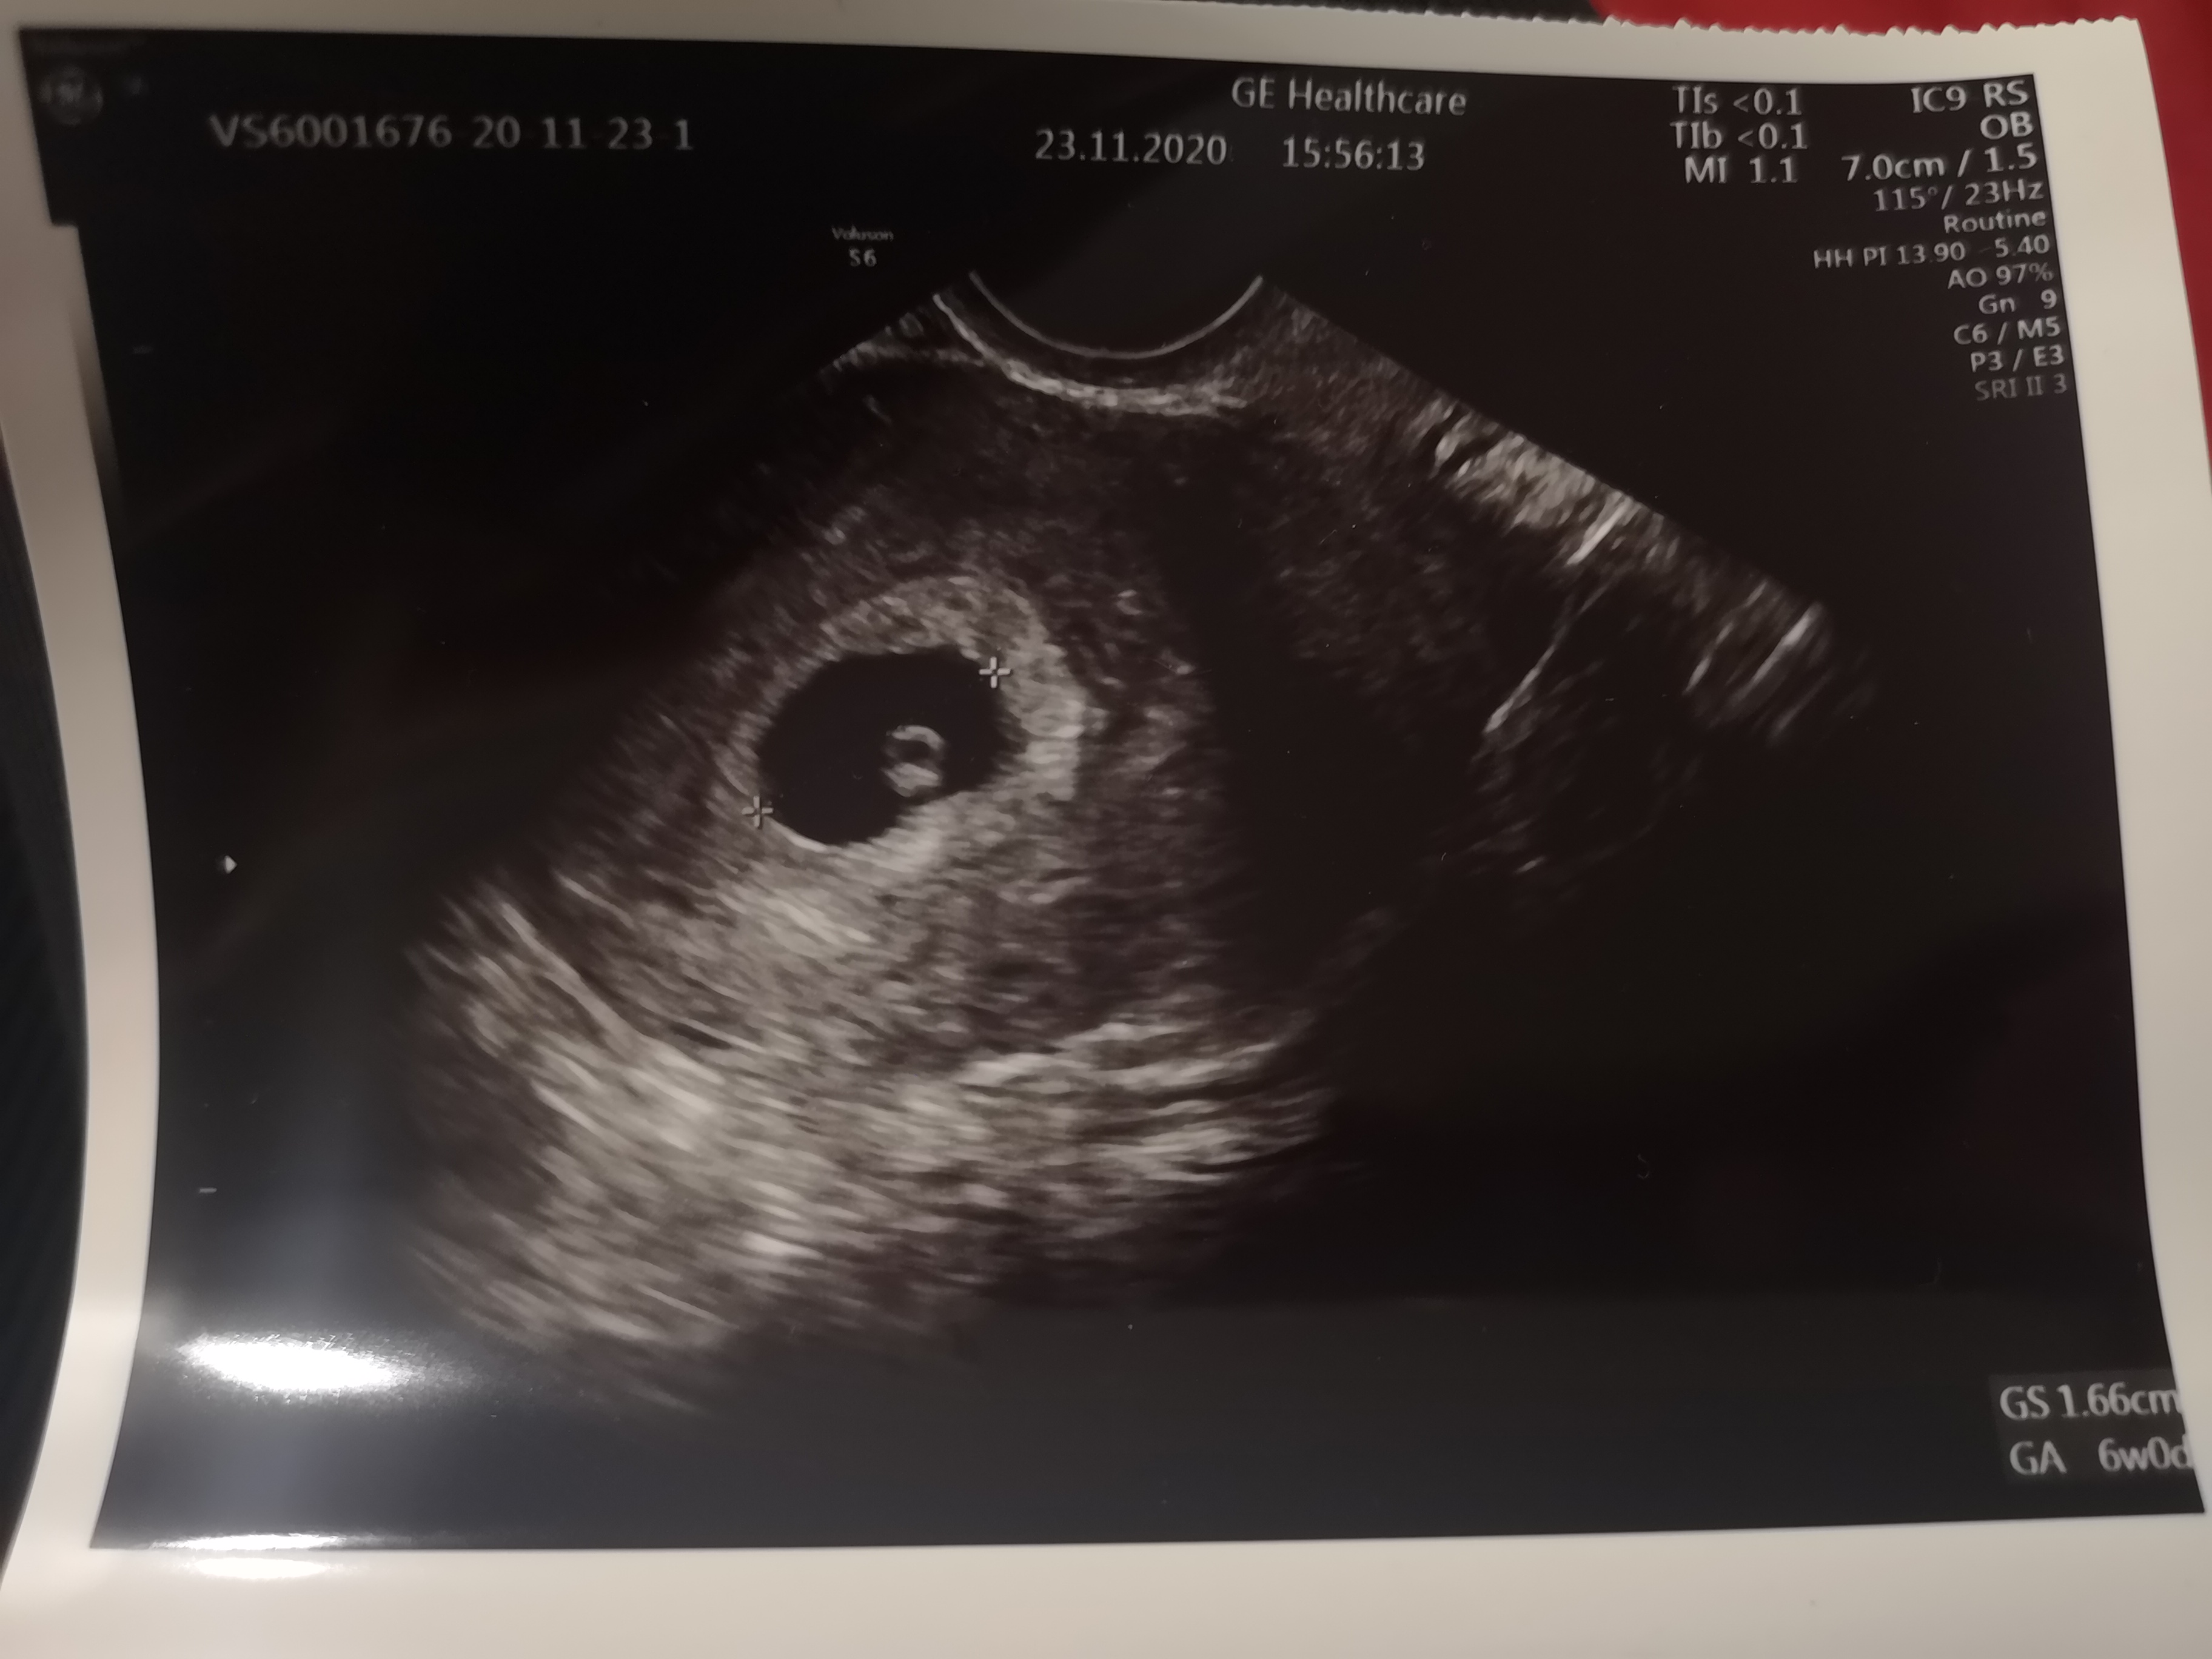

Nasze fasolki / USG

5+3, pęcherzyk z ciałkiem żółtym. :)